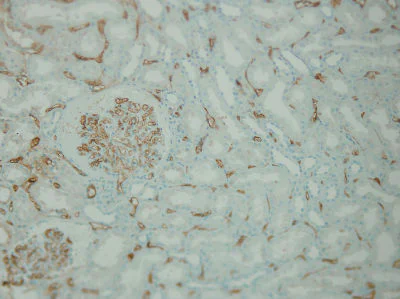

Immunohistochemical analysis of formalin-fixed, paraffin-embedded Human transplanted kidney tissue labelling C4d with ab136921 at 1/100 dilution showing diffuse strong positive immunostaining of peritubular and glomerular capillaries, indicating acute antibody mediated rejection.